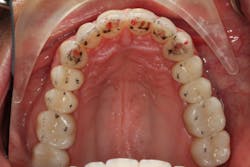

Our goal should always be to perform the least amount of dentistry needed to achieve the best possible functional results and satisfy the patient’s goals. Darren wasn’t interested in traditional orthodontics, so we elected to start with clear aligner therapy to increase the freedom in his envelope of function and improve the anterior occlusal relationship.

Orthodontics also allowed us to be more conservative in our tooth preparation. We wanted to minimize the amount of tooth structure that we had to reduce on the lingual of the maxillary incisors, since we were already missing a good amount of tooth structure from wear. Orthodontics also allowed the possibility to avoid any preparation or indirect restorations on the mandibular anterior teeth that otherwise would have been required to work out the anterior guidance. Darren was aware that we would need to make that final determination once the orthodontics treatment was completed.

Following the orthodontics, we prepared the maxillary arch for indirect restorations and placed Darren in temporary restorations. We also restored the mandibular incisal edges with direct composites to seal any exposed dentin and refine the incisal plane using a thermoplastic stent fabricated from our diagnostic wax-up. Utilizing a stent to place the direct composites on the incisal edges saved time, and we were able to obtain greater precision in the incisal edge position. Darren was then sent to the periodontist to have the gingival architecture corrected.

Darren remained in the provisionals for three months to allow the soft tissue to fully heal. This also allowed us to evaluate the esthetics, phonetics, occlusion, and function. The importance of provisional restorations cannot be understated, as they provide us with a trial before we place the definitive restorations.

The provisionals were especially important in this case as we had to work out the anterior guidance to be in harmony with the patient's envelope of function. When the provisional restorations were initially placed, Darren continued to feel “locked in” with the position and contours of his canines. Over several appointments, we had to slightly adjust his guidance until he was comfortable while still retaining the function and esthetics.